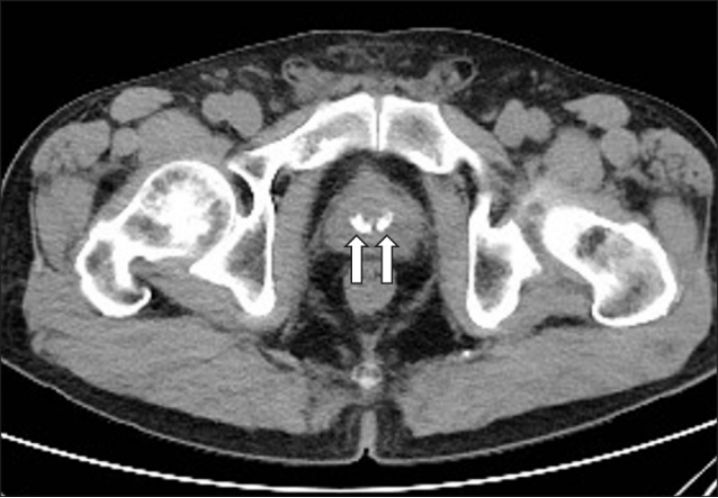

图为 CT中的前列腺结石

前列腺结石,顾名思义,就是前列腺里长结石了,与肾、输尿管里的结石不同,前列腺结石多见于50岁以上的中老年男性,且多无明显症状,常常在做体检(超声、CT检查等)时偶然发现,所以经常被称作“静石”。这种情况下无需特殊治疗,定期随访就行。